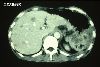

CT

病理学分类恶性上皮肿瘤/类基底细胞癌

病例的种类罕见病例